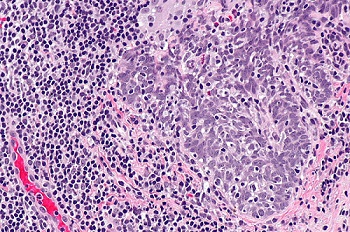

病毒入侵也会导致细胞或组织发生病理变化,如感染细胞与未感染细胞的胞浆膜发生融合,形成多核的巨细胞,或某些病毒感染细胞时,在光学明场显微镜下可见胞浆或胞核内出现嗜酸或嗜碱性染色、大小不同和数量不等的圆形或不规则的团块结构,如HPV人乳头状瘤病毒。

HPV引起,分化不良的鳞状细胞癌